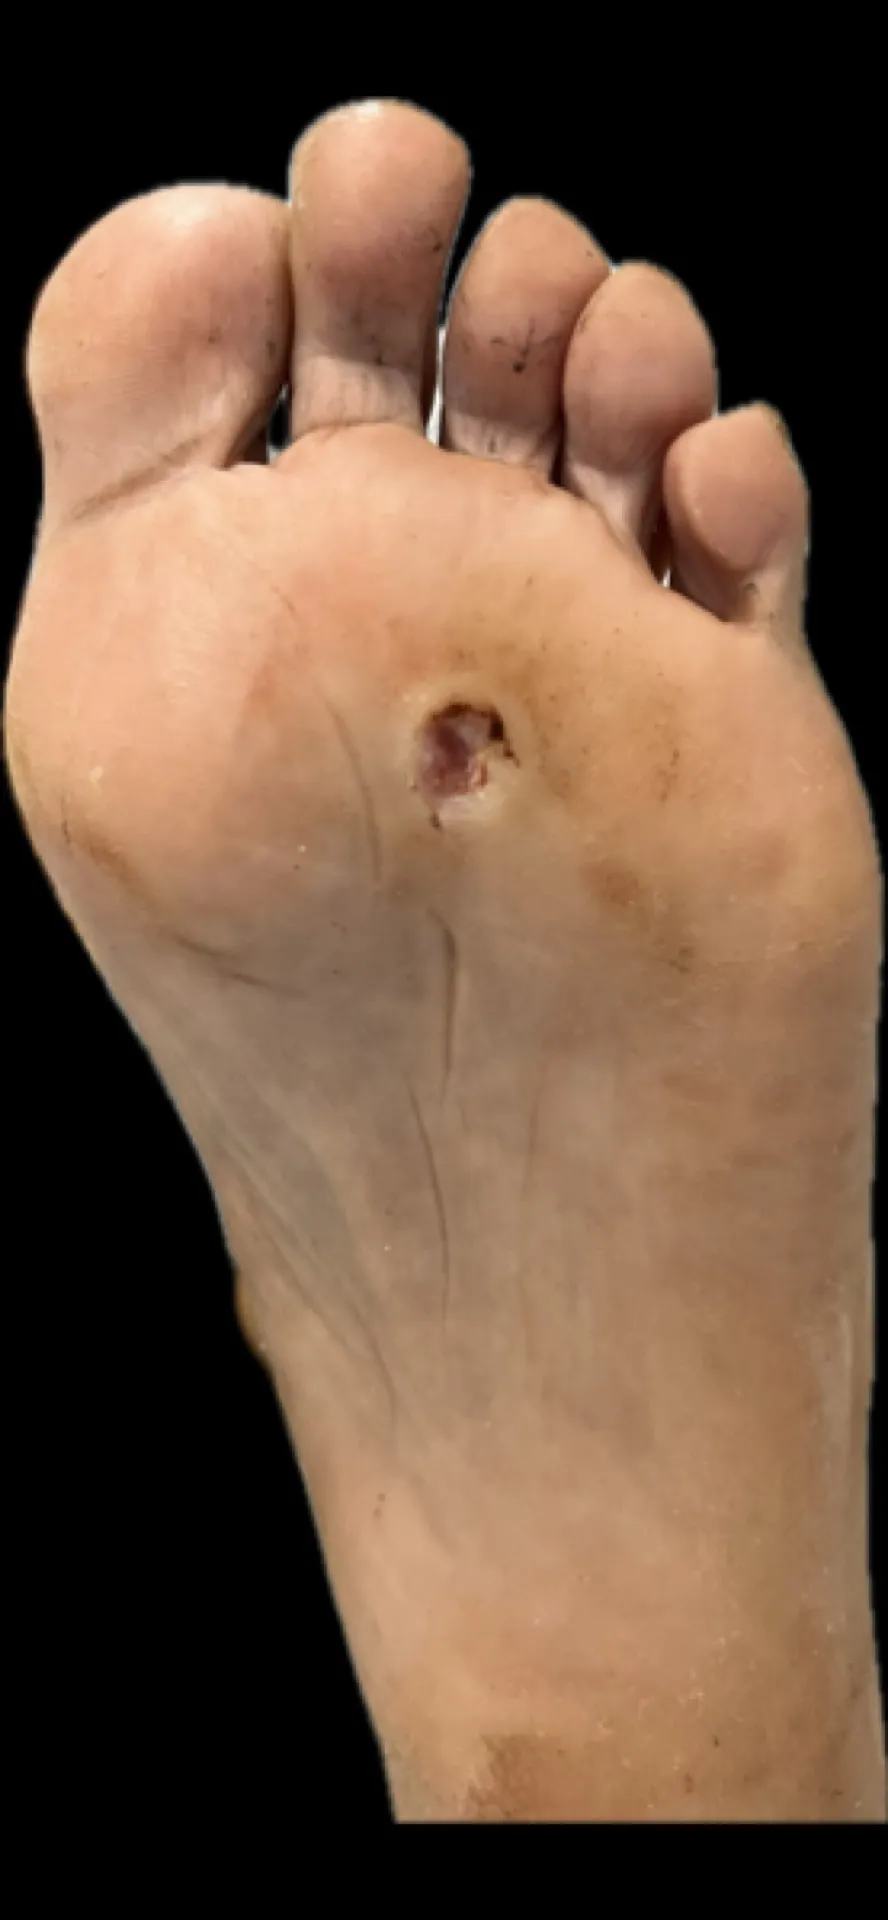

Figura 2: Aspecto clínico inicial. Observa la hiperqueratosis plantar bien delimitada en la zona metatarsal.

Lo que hacía este caso especialmente desafiante era la presentación bilateral: el pie derecho estaba afectado en la zona metatarsal central, mientras que el pie izquierdo presentaba la lesión en la zona del quinto metatarsiano.

Figura 3: Vista detallada de la lesión. El núcleo hiperqueratósico profundo es característico de la IPK.

- Lesiones bien delimitadas con núcleo hiperqueratósico profundo

Figura 5: Detalle de la lesión hiperqueratósica que causa dolor intenso tipo ‘clavo’ al caminar.